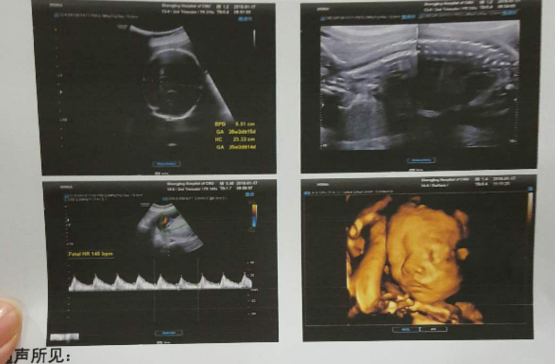

孕20周的检查,是“大排畸筛查”,也有的孕妈是直接做四维彩超,这样看的更清楚些,主要看宝宝的五官及内脏等是否存在畸形,这是孕期很重要的一次检查,因为看的项目比较多,所以检查时间也相对较长。

因为是做B超检查,检查是否存在畸形的同时,B超医生也会测量一些胎儿的数据,看胎儿的发育是否存在偏大或偏小的情况,如有医生,医生也会给出相应的建议。